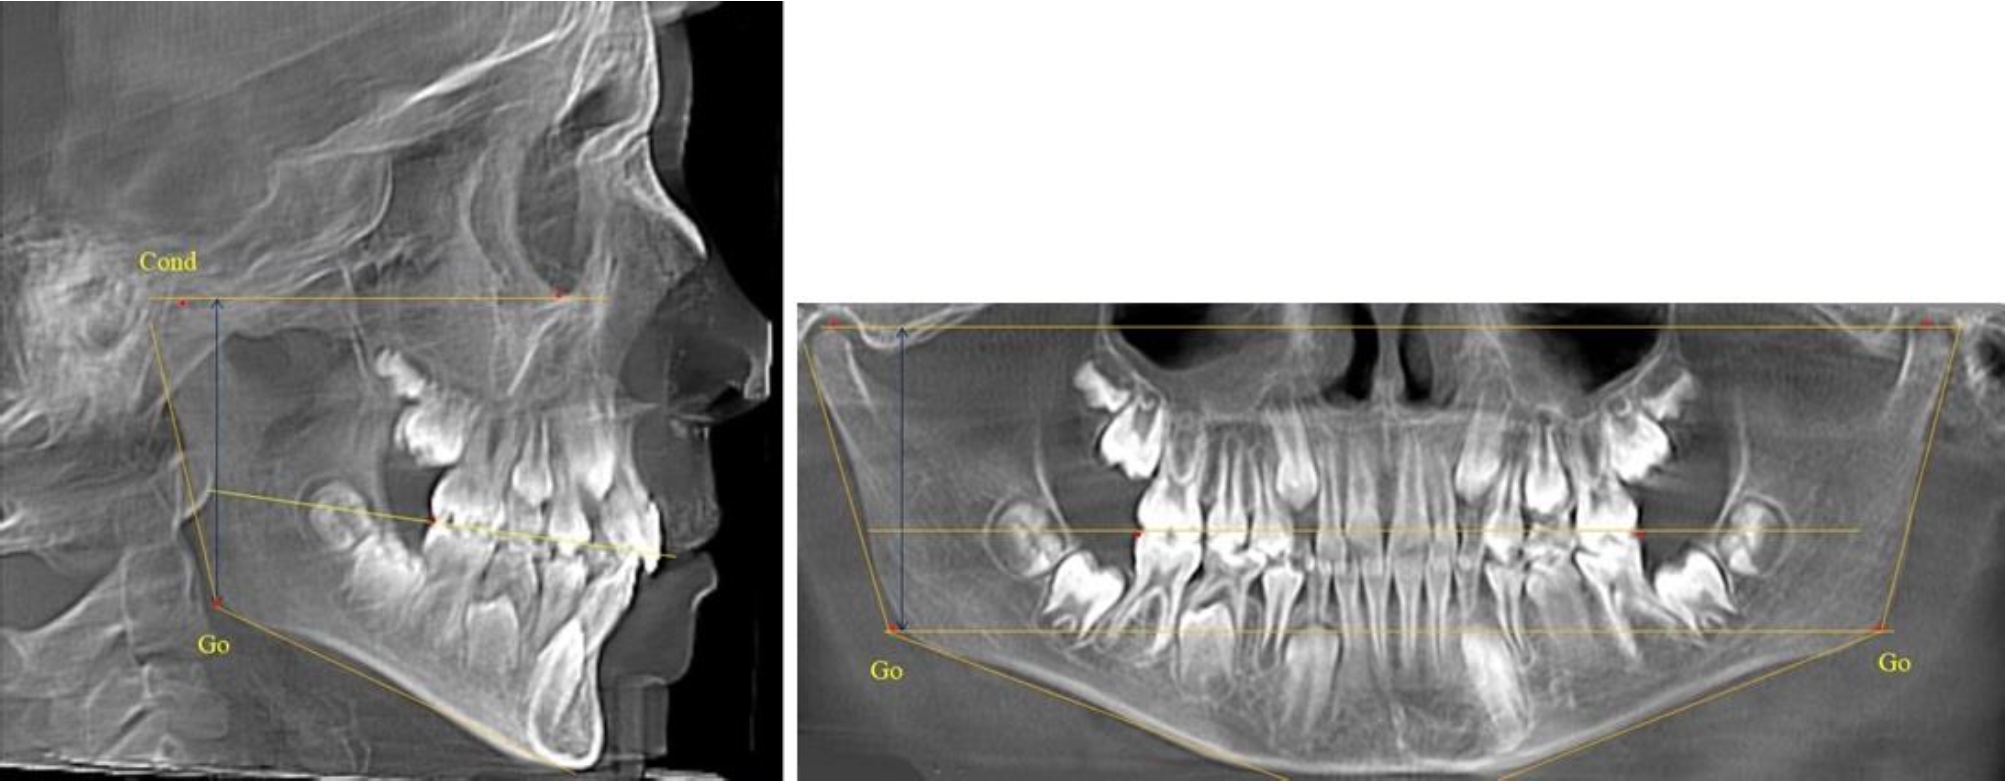

В 1-й группе были проанализированы 7 телерентгенограмм и 7 ортопантомограмм, что составило (6,60 ± 2,41) % от числа изученных рентгенограмм. На всех парах рентгенограмм угол нижней челюсти, измеренный на телерентгенограмме, соответствовал углу, полученному при построении угла на ортопантомограмме. Окклюзионная линия практически однотипно делила ветвь на два отдела (рис. 1).

Как на ортопантомограмме, так и на телерентгенограмме высота ветви у детей в периоде сформированного прикуса молочных зубов составляла (42,21 ± 2,48) мм. При этом высота верхней окклюзионно-суставной части была (22,57 ± 1,46) мм, а нижней – (19,64 ± 1,54) мм.

Учитывая вариабельность абсолютных величин, определи относительные показатели соразмерности частей ветви нижней челюсти. Так, отношение высоты верхней части ветви к нижней в среднем составляло 1,15 ± 0,13. Отношение общей высоты ветви к верхней ее части составляло 1,87 ± 0,14, а отношение общей высоты ветви к нижней ее части было 2,14 ± 0,16 и достоверных различий по относительному показателю отношения всей высоты к верхней и нижней челюсти нами не отмечено (р ˃ 0,05). При этом визуально обе части выглядели примерно равноразмерными.

Рис. 1. ТРГ и ОПТГ пациента 1-й группы

В 5-й группе были проанализированы 14 комплектов рентгенограмм, что составило (13,21 ± 3,29) % от общего числа. На всех рентгенограммах отмечен очередной этап подъема высоты прикуса, обусловленный прорезыванием вторых постоянных моляров. Окклюзионная линия делила ветвь на два отдела (рис. 5).

Рис. 5. ТРГ и ОПТГ пациента после смены молочных зубов и прорезывания вторых постоянных моляров

Высота ветви у детей 5-й группы составляла (62,87 ± 3,62) мм, что было достоверно больше, чем у детей других групп (р ˂ 0,05). При этом высота верхней окклюзионно-суставной части была (40,23 ± 2,01) мм, а нижней – (22,64 ± 1,78) мм. Высота верхней части была вдвое больше нижней, что и определяло особенности соразмерности частей ветви нижней челюсти в анализируемый возрастной период.

Относительные показатели соразмерности частей ветви нижней челюсти показали, что отношение высоты верхней части ветви к нижней в среднем составляло 1,78 ± 0,18. Отношение общей высоты ветви к верхней ее части составляло 1,56 ± 0,12, а отношение общей высоты ветви к нижней ее части было 2,78 ± 0,14, что и определяло особенности соразмерности частей ветви нижней челюсти в анализируемый возрастной период.